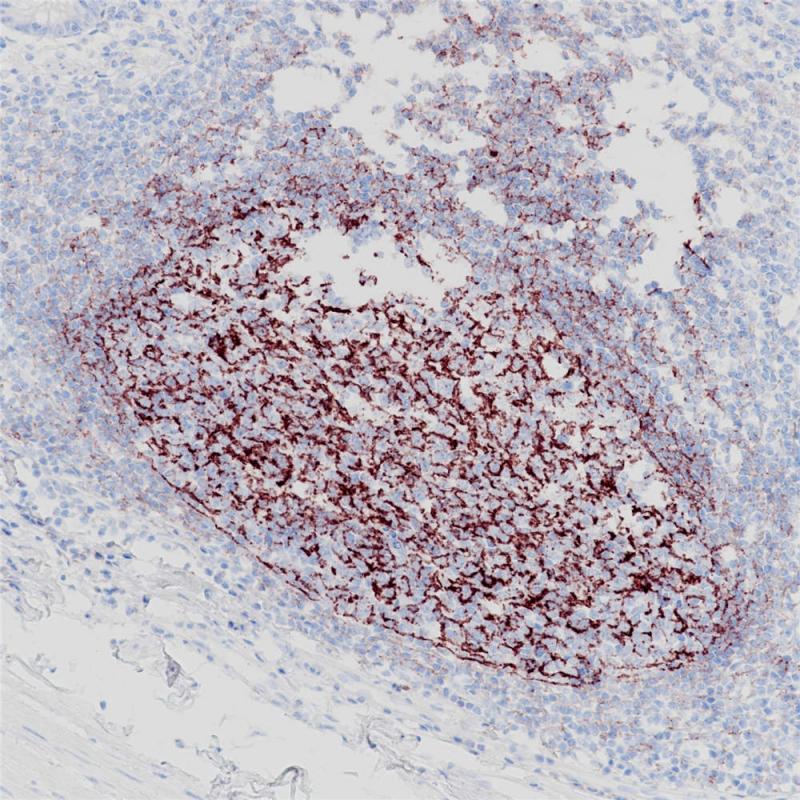

CD35又称补体受体1,是一种与膜结合的单体糖蛋白,在多种细胞表面表达,例如红细胞、白细胞、肾小球足细胞、滤泡树突网状细胞。CD35最主要的功能就是作为补体C3b和C4b的受体,起到对外来抗原的清除作用。CD35抗原存在于红细胞、B细胞、T细胞、单核细胞、嗜酸性细胞、中性粒细胞上。CD35抗体被认为是成熟B细胞的标志,可以标记滤泡树突细胞以及来源于此类细胞的肿瘤,如滤泡树突状细胞肿瘤/肉瘤。

阳性对照

扁桃体